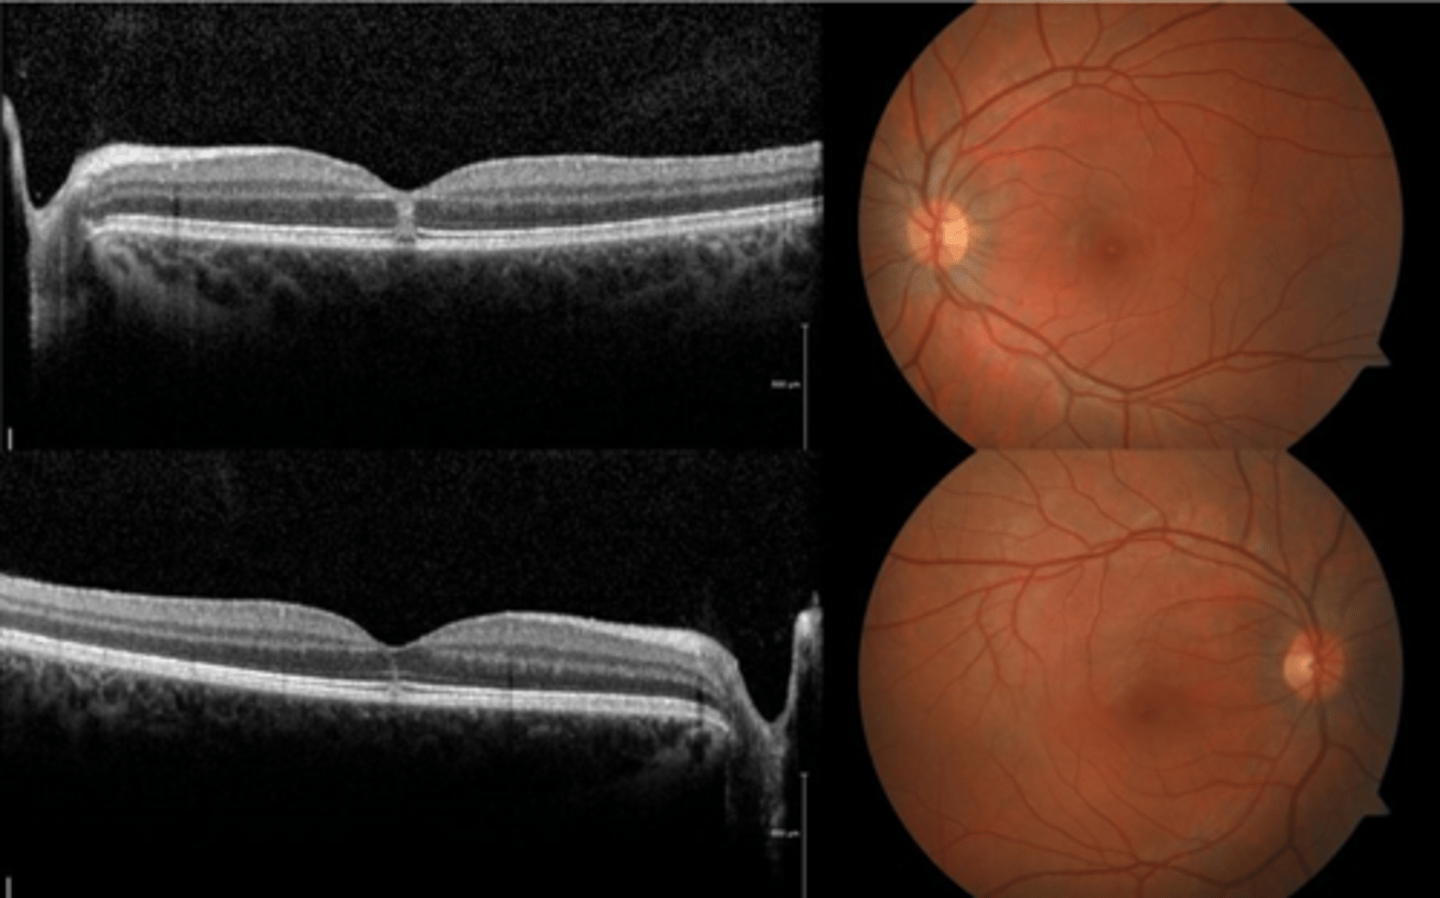

How does choroidal rupture appear on OCT here?

loss of RPE continuity at site of rupture = inner choroid atrophy

How does choroidal rupture appear on OCT here?

RPE disruption

+/- hemorrhage